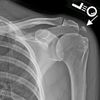

@attaradiology7373: آپ نے "5" لکھا ہے، یعنی آپ Mediastinal Tumors (سینے کے درمیانی حصے کے ٹیومرز) کے بارے میں جاننا چاہتے ہیں۔ نیچے مکمل تفصیل دی جا رہی ہے: ✅ Mediastinal Tumors کیا ہیں؟ Mediastinum سینے کا وہ حصہ ہے جو دونوں پھیپھڑوں کے درمیان ہوتا ہے۔ اس میں دل، غذائی نالی، تھائمَس غدود، لمف نوڈز، اور بڑے خون کی نالیاں شامل ہوتی ہیں۔ اس حصے میں کئی طرح کے ٹیومر بن سکتے ہیں — کچھ بے ضرر (benign) اور کچھ کینسر ی (malignant) ہوتے ہیں۔ 🧬 Mediastinal Tumors کی اہم اقسام 1. Lymphoma (لیمفوما) یہ لمف نوڈز میں بنتا ہے۔ دو بڑی اقسام: Hodgkin Lymphoma Non-Hodgkin Lymphoma 2. Thymoma / Thymic Cancer یہ Thymus gland میں بنتا ہے (عام طور پر سینے کے اوپر والے حصے میں)۔ 3. Germ Cell Tumors عام طور پر انڈاشیوں یا خصیوں میں بنتے ہیں، مگر سینے میں بھی ہو سکتے ہیں۔ 4. Neurogenic Tumors یہ اعصاب سے پیدا ہوتے ہیں، زیادہ تر بچوں میں دیکھے جاتے ہیں۔ 🔍 Mediastinal Tumors کے عام علامات عام طور پر ابتدا میں علامات نہیں ہوتیں، لیکن بڑے ہونے پر: سینے میں بھاری پن یا درد کھانسی سانس لینے میں دشواری آواز بیٹھ جانا وزن کم ہونا بخار یا رات میں پسینہ کھانا نگلنے میں دقت چہرے یا گردن پر سوجن (SVC Syndrome) 🧪 تشخیص (Diagnosis) Chest X-ray → ابتدائی اسکرین CT Scan / MRI → ٹیومر کی جگہ اور پھیلاؤ PET Scan Biopsy → حتمی تشخیص 🩺 علاج (Treatment) ٹیومر کی قسم اور اسٹیج پر انحصار کرتا ہے: ✔ سرجری Benign یا قابلِ نکال ٹیومرز کے لیے۔ ✔ کیموتھراپی خاص طور پر Lymphoma اور Germ cell tumors کے لیے مؤثر۔ ✔ ریڈییشن تھراپی ✔ Immunotherapy / Targeted Therapy کچھ خاص اقسام کے لیے۔ 📌 اگر آپ چاہیں تو میں آپ کو بتا سکتا ہوں: ✔ Mediastinal Lymphoma کی تفصیل ✔ Thymoma vs Thymic Cancer کا فرق ✔ CT Scan رپورٹ سمجھانا ✔ علاج کے مراحل کیا آپ ان میں سے کسی خاص ٹیومر کے بارے میں مزید جاننا چاہتے ہیں؟ #unfrezzmyaccount #healthylifestyle